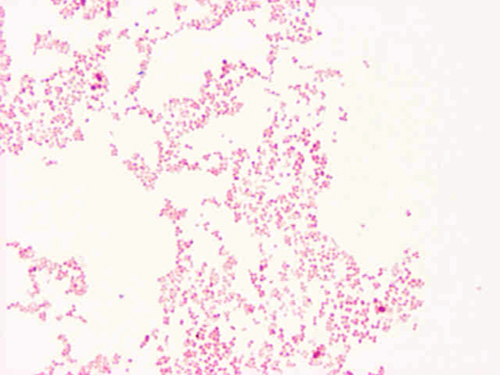

Note the very small gram negative cocci